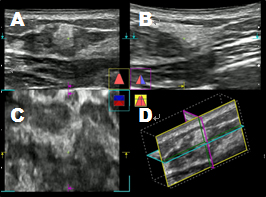

正常乳線の超音波像

Aが縦断面、Bが横断面、

Cが水平面、Dが立体構築した画像

乳線良性腫瘤の超音波像

Cが水平面、Dが厚み付き画像

乳線悪性腫瘤の超音波像

Aが通常像、Bがマイクロピュア像

小さな微小石灰化が描出されている。

乳線悪性腫瘤のエラストグラフィー像

周辺組織に比べて病変部は高い弾性を呈示している。